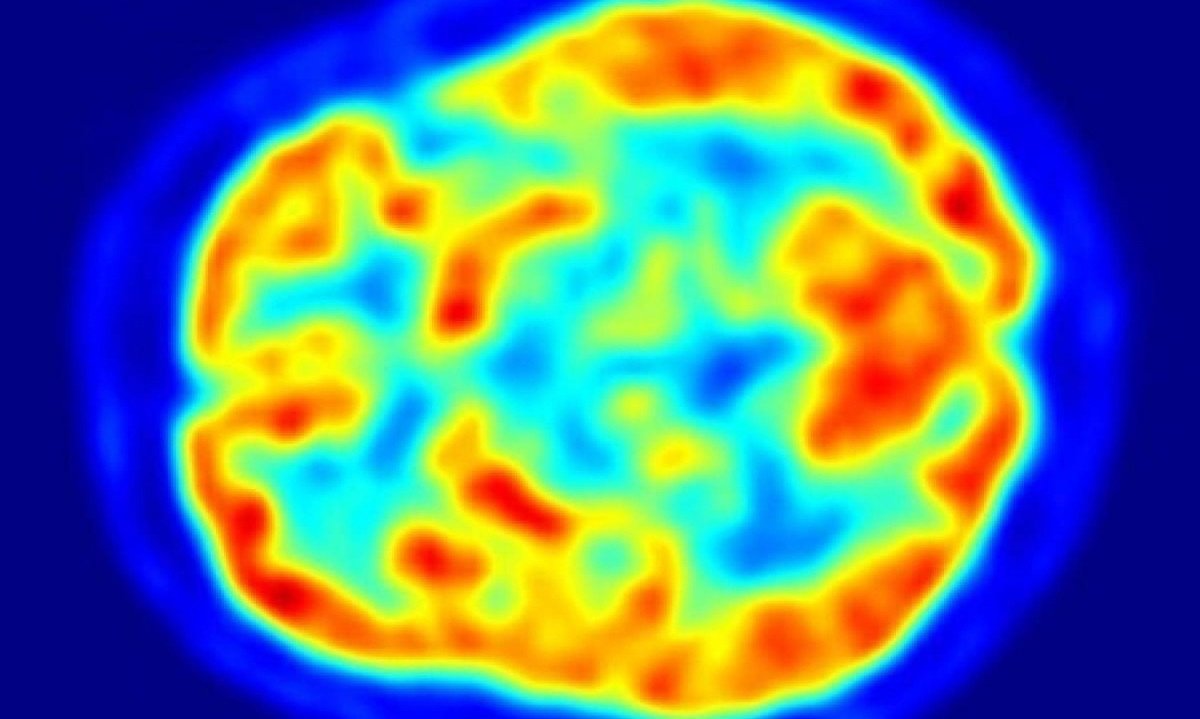

A partir de um estudo que analisou imagens cerebrais de mais de 2,5 mil pessoas com doença de Parkinson em 20 países diferentes, cientistas conseguiram identificar padrões de neurodegeneração e criar métricas para cada uma das cinco etapas clínicas da doença.

Fernando explica que na doença de Parkinson ocorrem alterações na estrutura cerebral dos chamados núcleos da base, ou gânglios basais – áreas do cérebro ligadas ao movimento automático. No entanto, o estudo permitiu comprovar a existência de alterações progressivas em outras áreas corticais, até então menos envolvidas na doença.

“Observamos que, conforme cada estágio da doença avançava, havia um grau maior de atrofia ou hipertrofia não só nas estruturas ligadas ao movimento, mas também em outras áreas corticais. E são essas combinações de atrofia e hipertrofia que estão relacionadas com o estágio da doença”, afirma.

“Mas não foi apenas isso que observamos, várias dessas estruturas apresentavam também diferenças na forma. Elas tinham alterado sua configuração espacial. Algumas regiões do tálamo [estrutura cuja função é retransmitir informações dos sentidos para o córtex cerebral] ficaram mais espessas. Outras regiões, como as amígdalas [que desempenham um papel na regulação do comportamento social e emoções] ficaram atrofiadas”, diz.

O pesquisador explica que essas alterações não são observadas a olho nu. “São medidas submilimétricas. No entanto, com programas e uso de inteligência artificial é possível identificar padrões e, no futuro, monitorizar essas alterações”, conta.